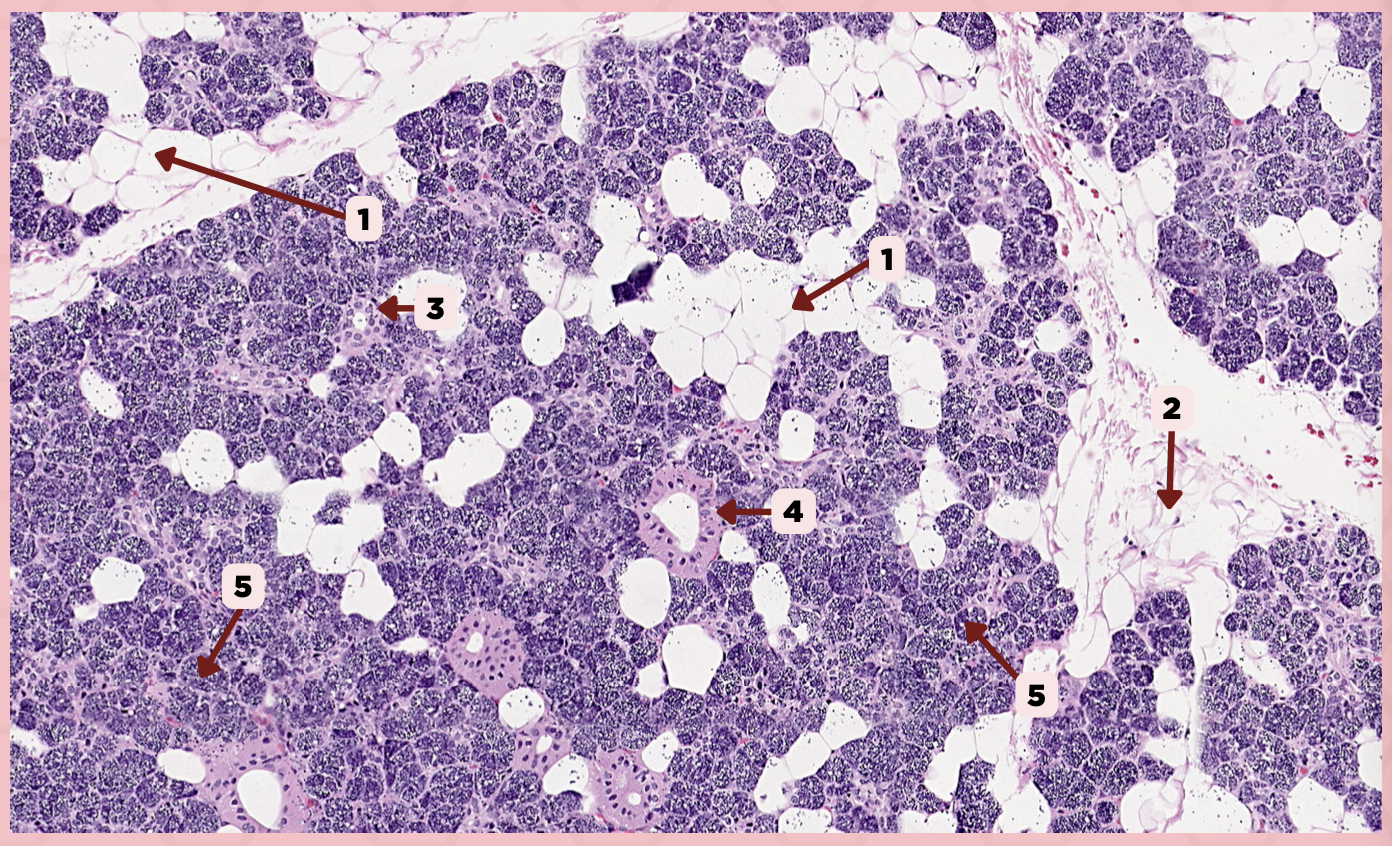

Parotid

Identify the specimen.

Adipocyte

Identify the structure labeled as 1.

Connective Tissue

Identify the structure labeled as 2.

Intercalated Duct

Identify the structure labeled as 3.

Striated Duct

Identify the structure labeled as 4.

Serous Gland

Identify the structure labeled as 5.